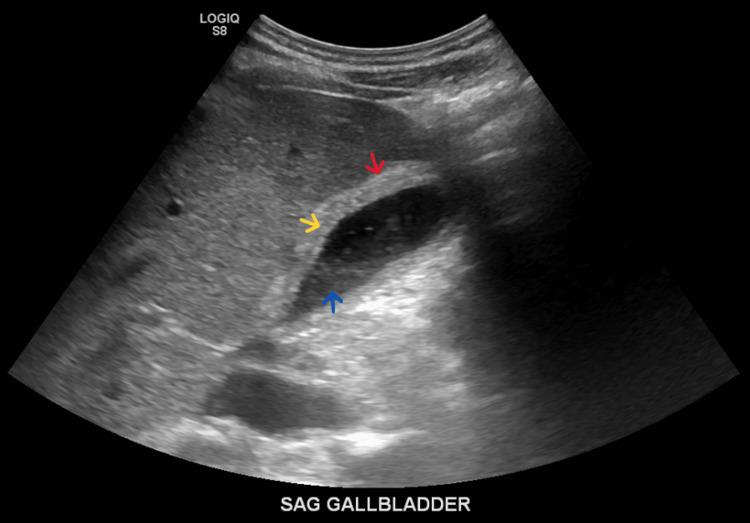

Angioimmunoblastic T-cell lymphoma (AITL) is a rare and aggressive form of peripheral T-cell lymphoma (PTCL). It can present with signs and symptoms that have broad differentials, including fevers, night sweats, and skin rashes. In this case report, we present an interesting case of a young male of Nigerian descent with recently treated malaria who presented with such symptoms and a picture that was complicated, due to an inconclusive excisional biopsy for lymphoma. He was later diagnosed with AITL. Given the patient's recent exposure to malaria, we will discuss the potential role malaria has in the development of AITL.

血管免疫母细胞性T细胞淋巴瘤(AITL)是外周T细胞淋巴瘤(PTCL)的一种罕见且侵袭性的类型。它可表现出具有广泛鉴别诊断的体征和症状,包括发热、盗汗和皮疹。在本病例报告中,我们呈现了一例有趣的病例,一名有尼日利亚血统的年轻男性,近期患疟疾并接受了治疗,他出现了上述症状,且由于淋巴瘤切除活检结果不明确,病情较为复杂。他后来被诊断为AITL。鉴于该患者近期感染过疟疾,我们将讨论疟疾在AITL发生发展中可能扮演的角色。